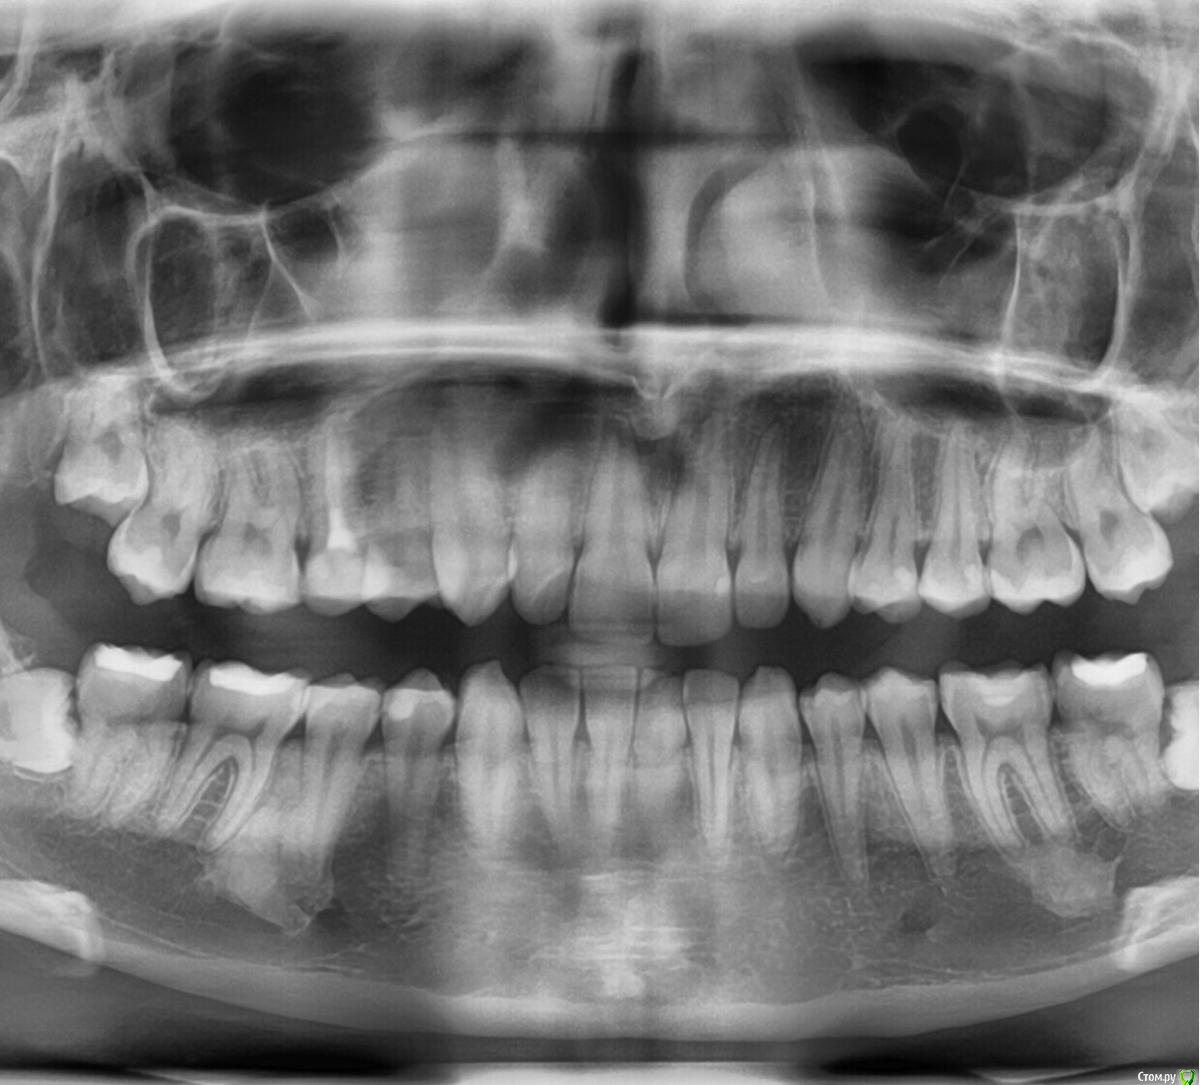

Кукушка357391 Опубликовано 6 сентября, 2019 Поделиться Опубликовано 6 сентября, 2019 (изменено) Добрый вечер.Я хочу устанавливать брекеты,мне сделали снимок и обнаружили два пятна слева.Скажите пожалуйста опасно ли это? Делала КТ в том числе. Нужно ли это удалять?И стоит ли мне ставить брекеты? Что худшее может быть? Я очень очень сильно переживаю.Сказали, что такое очень редко встречается.В интернете на эту тему информации очень мало.Помогите мне пожалуйста. Изменено 6 сентября, 2019 пользователем Кукушка357391 Ссылка на комментарий

krokomot Опубликовано 7 сентября, 2019 Поделиться Опубликовано 7 сентября, 2019 НИчего опасного, это участки гиперостоза. Живите и ставте бреккеты спокойно. Ссылка на комментарий

Кукушка357391 Опубликовано 7 сентября, 2019 Автор Поделиться Опубликовано 7 сентября, 2019 НИчего опасного, это участки гиперостоза. Живите и ставте бреккеты спокойно.Сегодня сказали,что возможно остеомаГиперстоз и остеома это не одно и тоже? Ссылка на комментарий